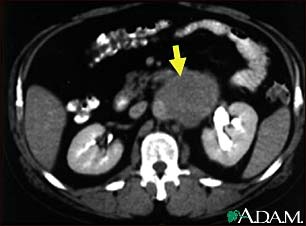

A CT scan of the middle abdomen showing a large tumor mass due to metastasis (spreading cancer) in abdominal lymph nodes.